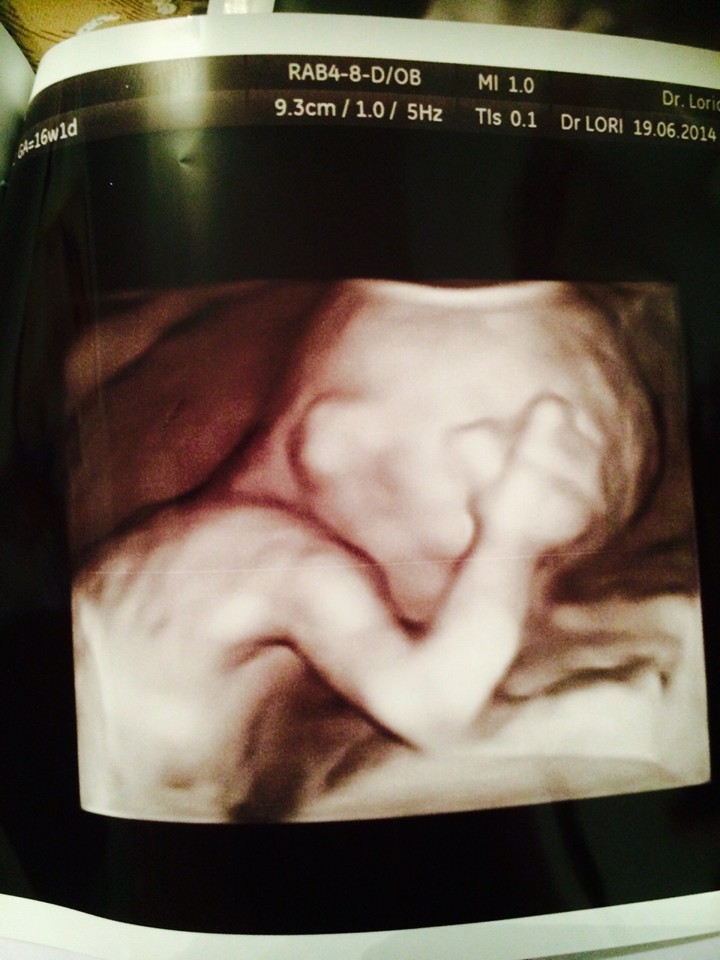

А первое слово, конечно, было «Мама». Лиат  хранит снимок  ультрасаунда  Йоси, еще до его появления на свет.